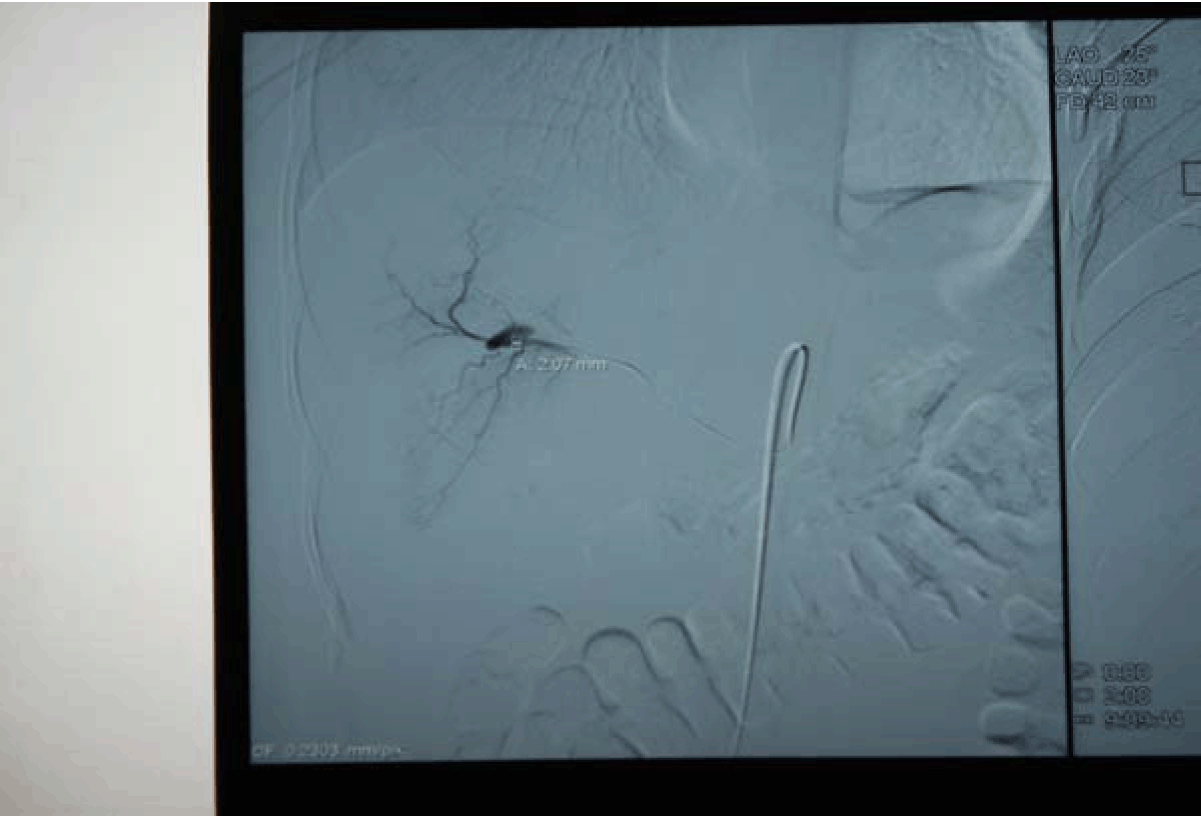

A 27-year-old male presented with complaints of one episode of hematemesis seven days back and melena for seven days. There was a history of roadside accident one and a half months before with grade IV liver injury, revealed on computed tomography (CT) scan of the abdomen. Patient was managed conservatively in Department of Surgery and discharged from hospital after one week in stable condition. On examination, the patient was anemic, pulse 110/min, blood pressure 80/50 mmHg with postural fall in blood pressure. The systemic examination was normal. Clinical possibility of upper GI bleed was kept. Emergency investigation revealed hemoglobin 4.5 g/dL, TLC 4900/mm3. BU 30 mg%, S. cr.-1.0 mg%, and electrolytes Na-135 mEq /L, K-4.1 mEq/L, Cl-105. The nasogastric tube drainage was persistently revealed altered blood. The patient was stabilized with three units of blood transfusion and emergency esophagogastroduodenoscopy was done. The esophagogastroduodenoscopy revealed alerted blood in the stomach with large clot in the fundus but source was not evident, first and second part of duodenum was also normal, but blood was present. On visualizing the ampulla, there was evidence of blood coming from ampulla. Emergency computed tomography angiography revealed pseudoaneurysm in segment VIII of liver involving segmental branches of right hepatic artery with active bleeding with communication with biliary radicals, with blood in gallbladder, common bile duct and second part of duodenum with subcapsular hematoma in segment VIII. (Figure 1) The digital selective arteriography revealed pseudoaneurysm from segmental branches of right hepatic artery. (Figure 2) Embolization was done and post embolization digital selective arteriography revealed complete non opacification of pseudoaneurysm. (Figure 3)

Figure 2: Digital selective arteriography showing pesudoaneurysm in segmental branches of right hepatic artery.